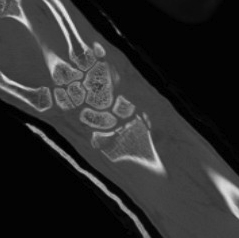

Dislocated Radiocarpal Joint CT 1Dislocated Radiocarpal Joint CT 2Dislocated Radiocarpal Joint CT 3